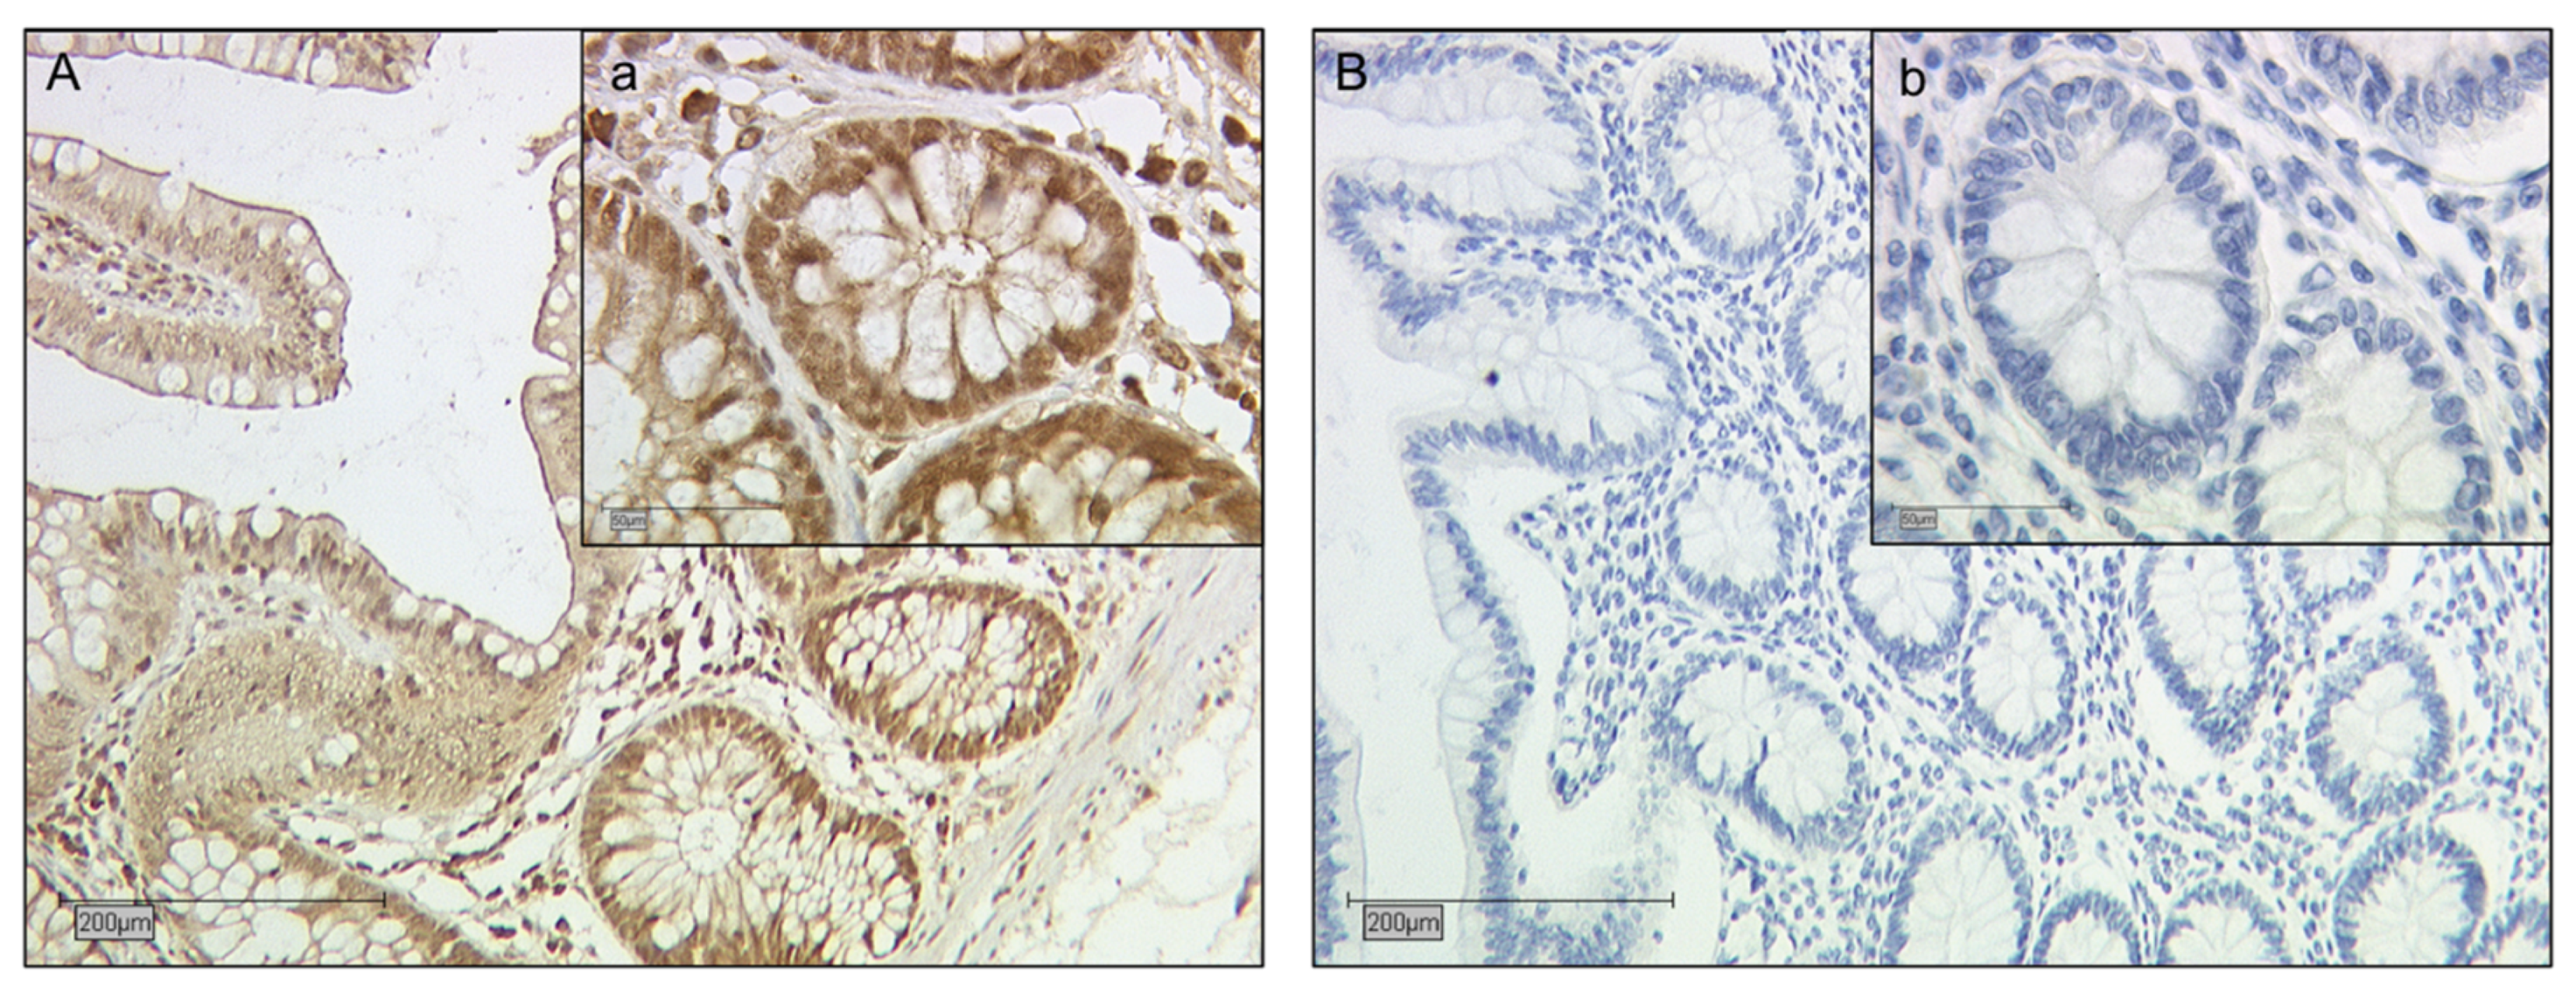

2.2. Galectin-2 Expression Is Upregulated in the Fetal Syncytiotrophoblast of GDM Placentas

2.5. Identification of Galectin-2 Expressing Cells by Immunofluorescence Double Staining

4.2. Immunohistochemistry

4.2.1. Staining